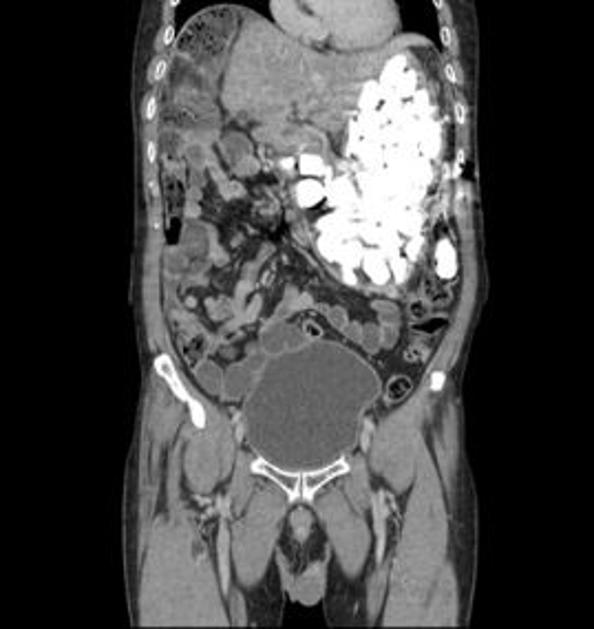

CT želodca American Journal of Medical Case Reports CT želodca

Dva kilograma kamenja v želodcu moškega American Journal of Medical Case Reports Dva kilograma kamenja v želodcu moškega